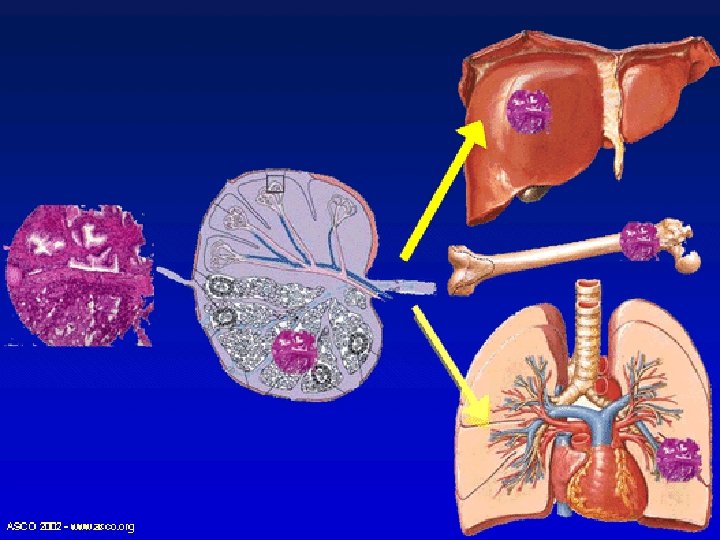

Surgery for Metastatic Disease metastases to: -lung -brain -liver can be controlled by surgical resection -

Metastasectomy This is done when: • The primary tumor is controlled or can be controlled • Metastasis is single or multiple • Evidence that metastasectomy is associated clinical benefits • Tumor doubling time is sufficiently long • No significant co-morbid factor

Metastasectomy • Complete resection of distant metastases improves five-year overall survival rates • 40% for colorectal cancer with resection of liver metastases • 30% for sarcoma with resection of lung metastases • 16% for breast cancer with resection of brain metastases